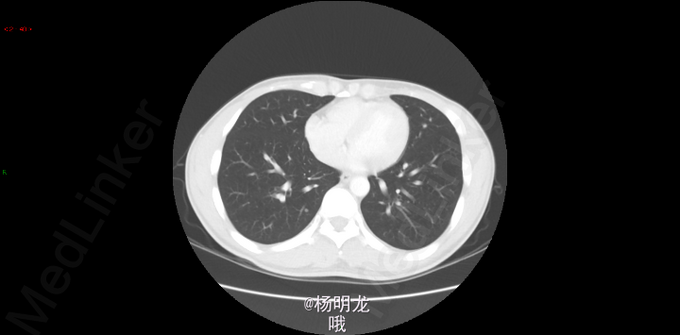

2014.9因大便带血,行肠镜检查,病理提示直肠癌。 2014-10-8胸部CT:双肺新出现多发微小结节,大者约0.2cm,高度警惕肺内转移。 遂于我院行FOLFIRI方案化疗,10周期。